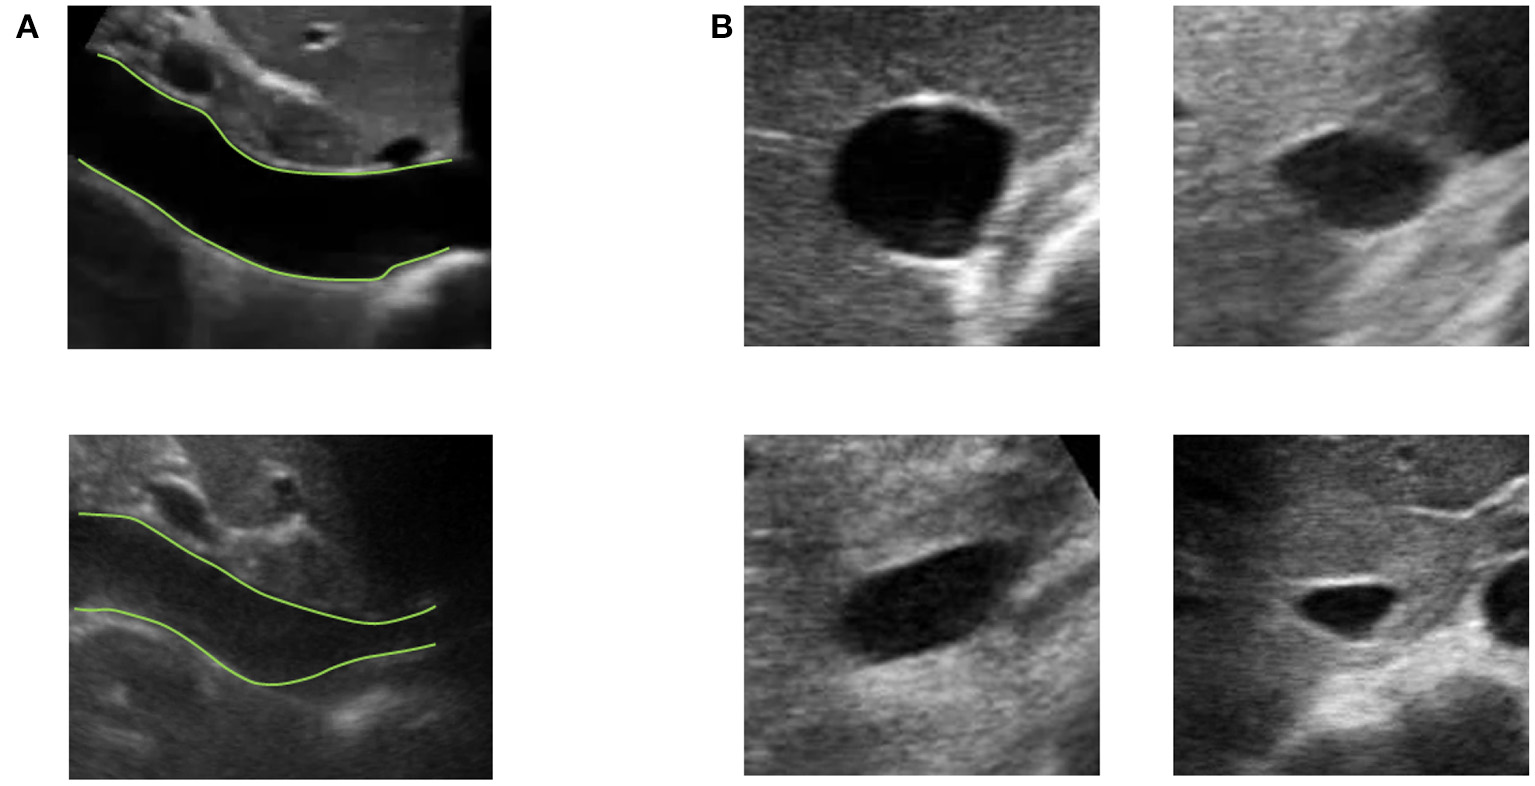

Vessels such as the IVC might have a complex geometry. In particular, as shown in Figure 3, the section of the IVC is not constant along the longitudinal axis and its cross-section is far from being like a perfect circle, with large variations across subjects and clinical conditions. Moreover, IVC is a very compliant vessel whose movements are also affected by surrounding structures to which it can be anchored. Therefore, measuring its size on a single plane might be largely inaccurate (as shown in Figure 4).

Figure 3

Examples of long and short axis sections of inferior vena cava (IVC) from different subjects. (A) IVC in long axis: one IVC has a stable diameter whereas the other shows great variations along the longitudinal axis. (B) Different shapes of IVC cross-sections.